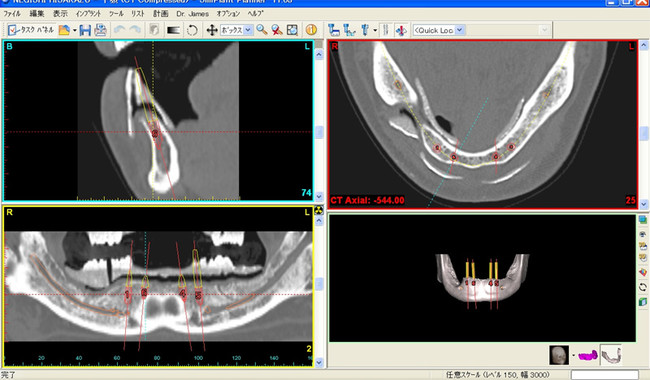

下顎の骨の中を通っている大きくて、太い神経です。インプラント治療や親知らずの抜歯の時には、注意が必要です。

左下のレントゲン画像では、黒く長い曲線の部分にあたります。